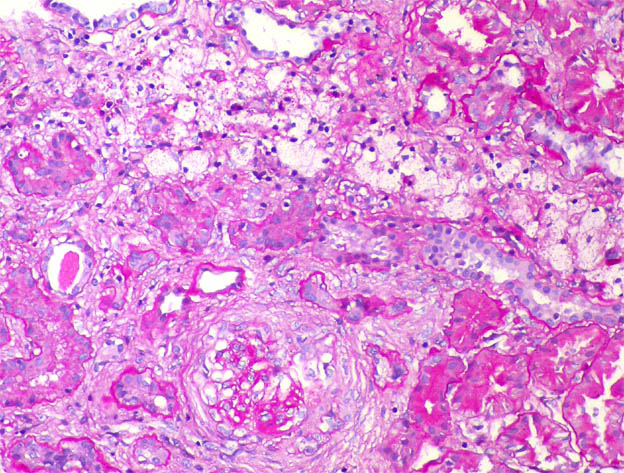

The patient is a 11-year-old boy with a history of steroid-resistant nephrotic syndrome since he was 7 years old. Renal biopsy at 8 years was diagnosed as focal segmental glomerulosclerosis (in another center, we do not have histological images). He continues with nephrotic syndrome since and now the serum creatinine has increased: 1.4 mg/dL. A new renal biopsy is undertaken to see the severity of the histological changes and decide whether to try another immunosuppressant treatment.

See the images of the second renal biopsy.

Figure 8. PAS, X400.